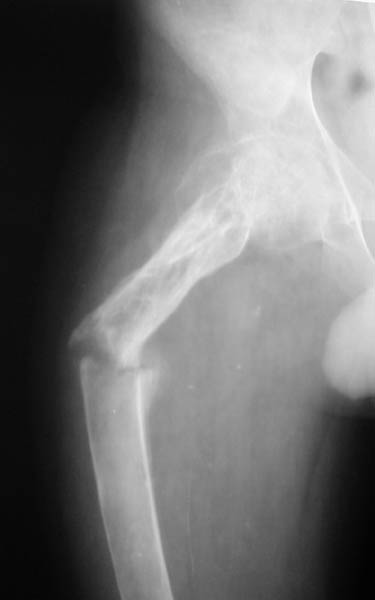

Мальчик, 14 летЖалобы на боли в правом бедре, резкое ограничение активных и пассивных движений в тазобедренном и коленном суставах справа, вынужденное положение правой ноги. Диагноз: Хондрома проксимального отдела правого бедра, состояние после внутриполостной резекции и аллопластики, закрытый патологический перелом проксимального отдела правого бедра со смещением В 2001 г. - хондрома проксимального отдела правого бедра. Операция - внутриполостная резекция, аллопластика. В течение 2 лет - 2 патологических перелома (СВ, гипс). 23.04. - закрытый патологический перелом проксимального отдела правого бедра.Патогистологическое исследование от 06.05.: остеобластома, диагноз в пользу агрессивного варианта.Тактика лечения?С уважением,А.В.ВладзимирскийДонецкий НИИ травматологии и ортопедииДонецк, Украина

Нельзя ли показать другую проекцию, а то в приложении две фотографии одной и той же рентгенограммы.